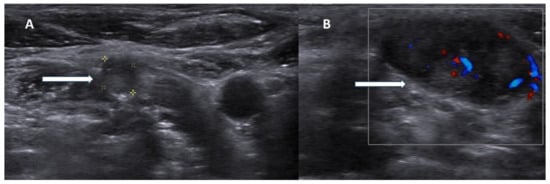

Sonographic features indicative of PC typically include lesion size greater than 3 cm, substantially larger than typical benign adenomas, which generally measure 1–2 cm. Malignant lesions often exhibit irregular or lobulated margins with evidence of invasion into adjacent tissues, in contrast to the smooth, well-circumscribed borders characteristic of benign counterparts (Figure 1).

Figure 1. Ultrasonography image of parathyroid carcinoma. Legend: 65-year-old patient with parathyroid carcinoma presented with serum PTH of 1300 pg/mL (12–88 pg/mL) and Ca:13 mg/dL (8.8–10.6 mg/dL). Ultrasonography showed a hypoechoic mass with lobulated borders (32 × 23 × 14 mm) next to the lower pole of the left thyroid lobe (blue arrow). The white arrow shows the inferior thyroid artery.

Additional suspicious findings include a heterogeneous echotexture with marked hypoechogenicity, reflecting necrosis, hemorrhage, or fibrosis, and a depth-to-width ratio of ≥1, as malignant lesions tend to be taller than wide. The presence of intralesional calcifications and cervical lymphadenopathy further strengthens the suspicion for carcinoma [2,15,16] (Figure 2).

Figure 2. Ultrasonography images of parathyroid carcinoma neck metastases. Legend: 70-year-old patient presented with parathyroid carcinoma lymph node metastases with hypoechoic lesions without fatty hilum ((A), white arrow) and chaotic blood flow in Doppler imaging ((B), white arrow).

However, these sonographic characteristics often overlap with those of large or atypical benign adenomas, and no single US feature is pathognomonic for malignancy. Conventional US achieves a sensitivity of approximately 76.1% and a positive predictive value (PPV) of approximately 93.2% for identifying parathyroid lesions [17], yet its ability to distinguish benign from malignant pathology remains limited. Moreover, as an operator-dependent technique, US demands substantial experience and specialized expertise in parathyroid imaging to ensure accuracy and reproducibility (Table 1).